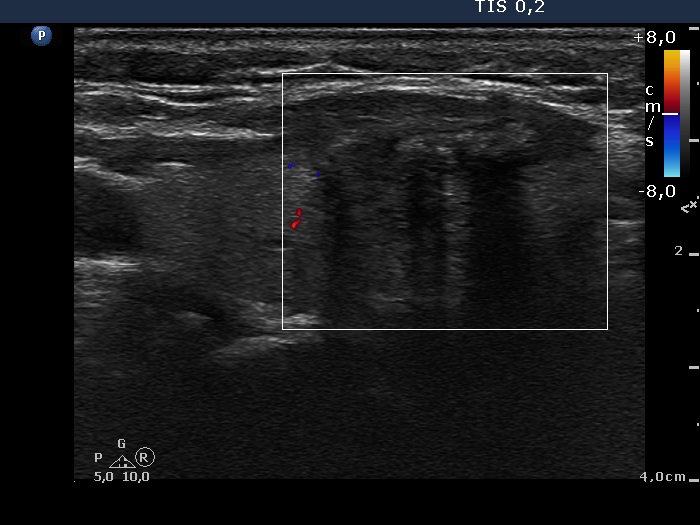

Left lobe, longitudinal view, color Doppler mode.